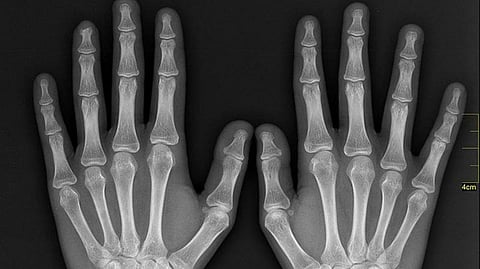

أكد رئيس قسم علوم الحاسب والذكاء الاصطناعي في جامعة جدة الدكتور محمد القحطاني، أن "الجيل القادم للأنظمة الذكية"، عبارة عن مشروع لاكتشاف الكسور باليد عبر الذكاء الاصطناعي؛ لتفادي الأخطاء الطبية وتقليل التكلفة المادية.

أما عن آلية عمل المشروع، فقال القحطاني إن مشروع اكتشاف الكسور باليد تم تصميمه بحيث يتم إدخال صورة الأشعة وحينها يقوم الجهاز بتقنية الذكاء الاصطناعي باكتشاف مكان الكسور مباشرة.